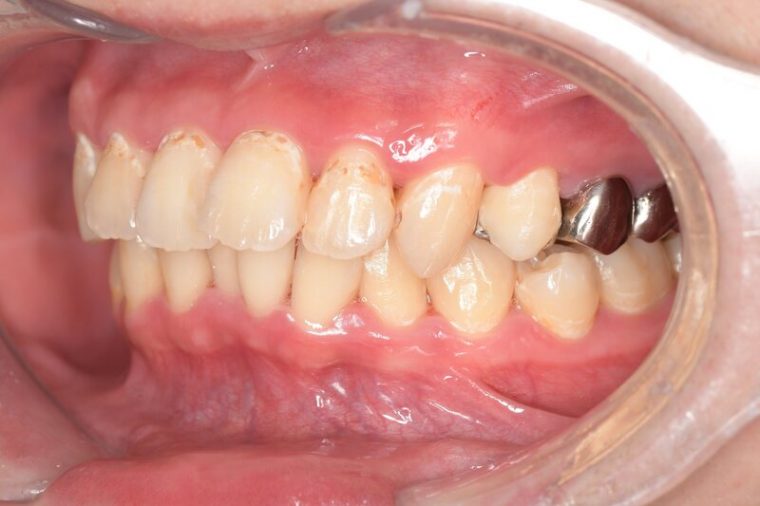

CASE 4

| 年齢・性別 | 52歳・女性 |

|---|---|

| 主訴 | クリーニングしたい |

| 治療内容 | スケーリング・PMTC |

| 治療期間 | 60分 |

| 治療費 | 約7,000円 |

| リスク・副作用 | 知覚過敏、歯肉退縮 |

| 治療方針 | 歯石とステインを除去して、今後は定期検診でのクリーニングと併せてガムピーリングやホワイトニングを行います。 |

| 担当者所見 | 歯肉の色素沈着が目立つため、ガムピーリングを行いながらホワイトニングを行うことをおすすめします。 |